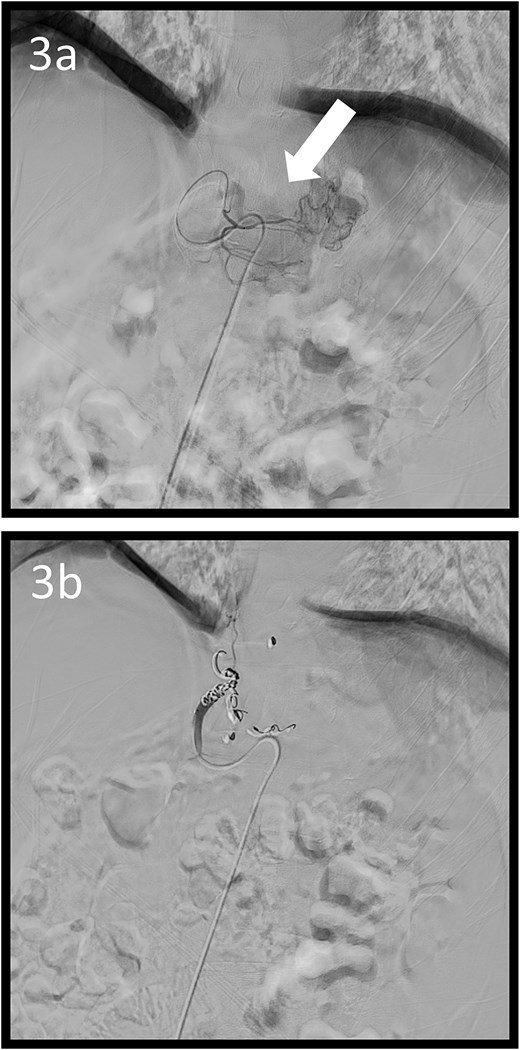

Angiographic images; (a) the left gastric arteriography showing tumour staining (arrow); (b) the left gastric artery was coil embolized.

A 59-year-old man presented to the emergency department with loss of consciousness and hematemesis. His blood pressure was 90/50 mmHg. The patient’s haemoglobin level was 7.9 g/dL. The patient was haemodynamically unstable, and 12 units of red blood cell (RBC) concentrate were administered. Contrast-enhanced computed tomography (CT) revealed a gastric hyper-vascular mass on the lesser curvature (Fig. 1). Emergency upper gastrointestinal (GI) endoscopy performed under endotracheal intubation and ventilatory management revealed a large type 1 oozing tumour (Fig. 2a). Haemostatic procedures were not performed due to technical difficulties. Emergency angiography revealed a tumour stain from the left gastric artery, which was coil embolized (Fig. 3). Upper GI endoscopy 2 days later revealed no bleeding (Fig. 2b). After embolization, the patient became haemodynamically stable. It was later discovered that he had undergone open omental filling at another hospital 1 year prior due to GC perforation and left his disease untreated for a year at his own discretion. The patient received combination chemotherapy with S-1 and oxaliplatin, which was remarkably effective. Eight months after embolization, laparoscopic total gastrectomy with Roux-en-Y reconstruction and lymph node dissection were performed. The final histopathological diagnosis was T2N0M0 stage IB. Macroscopic findings revealed a type 1 tumour in the upper part of the stomach. Histopathological findings revealed that the tumour was a well-differentiated tubular adenocarcinoma. All surgical margins were negative. The patient had an uneventful postoperative course and was discharged 7 days after surgery. The patient was well, with no recurrence noted during the 35 months of follow-up.